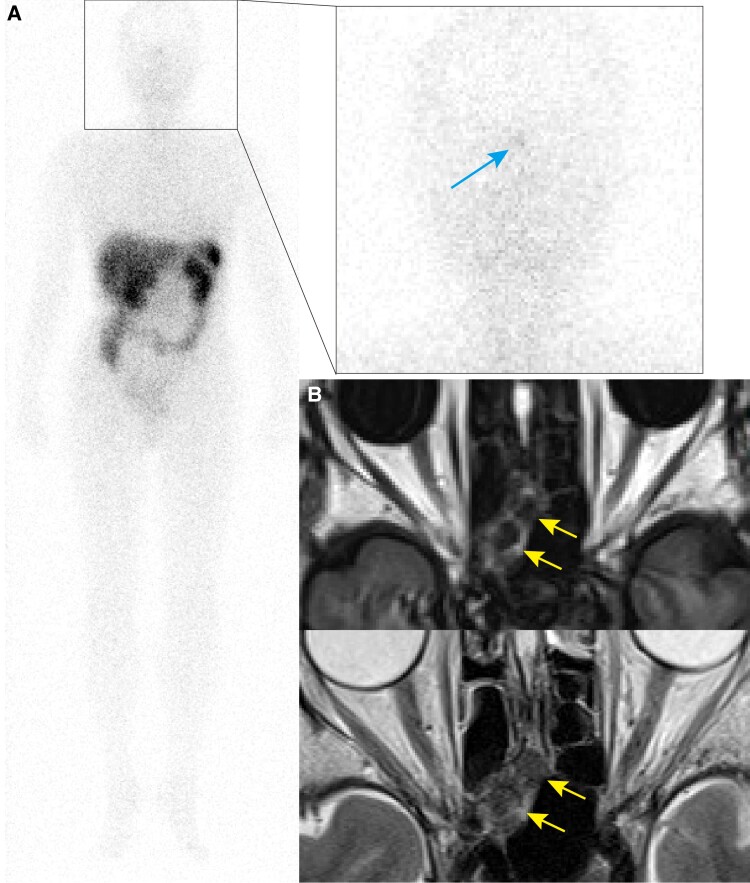

Tumor-induced osteomalacia is characterized by hypophosphatemia and fragility fractures caused by fibroblast growth factor 23 (FGF23)-producing tumors. We report a case of tumor-induced osteomalacia in which the tumor location could be determined by gallium 68 (68Ga)-DOTATOC positron emission tomography (PET)/computed tomography (CT). A 74-year-old woman had recurrent fractures and bone pain. Blood tests showed hypophosphatemia and elevated serum alkaline phosphatase and FGF23 levels and CT and bone scintigraphy showed multiple bone fractures. Tumor-induced osteomalacia was therefore suspected. Indium 111 (111In)-pentetreotide scintigraphy showed focus of increased activity in the head, and CT and magnetic resonance images showed a mass-like lesion in the posterior ethmoidal sinus. However, in systemic venous sampling, serum FGF23 level was highest in the left common iliac vein. 68Ga-DOTATOC PET/CT clearly demonstrated focal uptake in the left anterior inferior iliac spine consistent with systemic venous sampling. Retrospectively analyzed, focal uptake in the head was considered to be a physiological uptake in the pituitary gland. The tumor was resected and the pathological diagnosis was phosphaturic mesenchymal tumor. A combination of systemic venous sampling and 68Ga-DOTATOC PET/CT was useful in detection of a small FGF23-producing tumor. Precise tumor localization in such cases requires careful interpretation of scintigraphy.